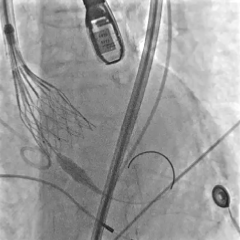

术中影像

第一次展开,瓣膜形态敞口

第二次展开,瓣膜位于0位;此时患者发生室颤,除颤后进行按压